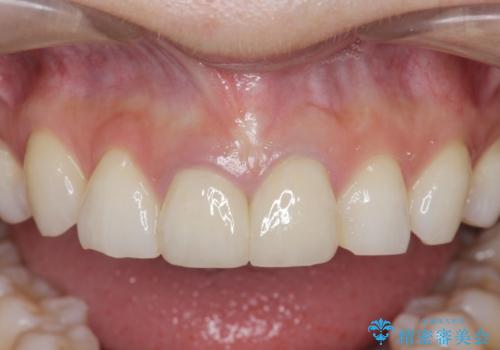

- 「幼少期に転んで治療した前歯がうずく、疲れると膿が出る。」と治療を希望され来院されました。

X線写真検査に加え圧痛、打診痛が認められたため、慢性根尖性歯周炎と診断し、根管治療から行うセラミック治療を計画します。

今回は根尖性歯周炎に対する根管治療を行ったことで症状は改善し、快適に食事ができる状態へと改善しました。